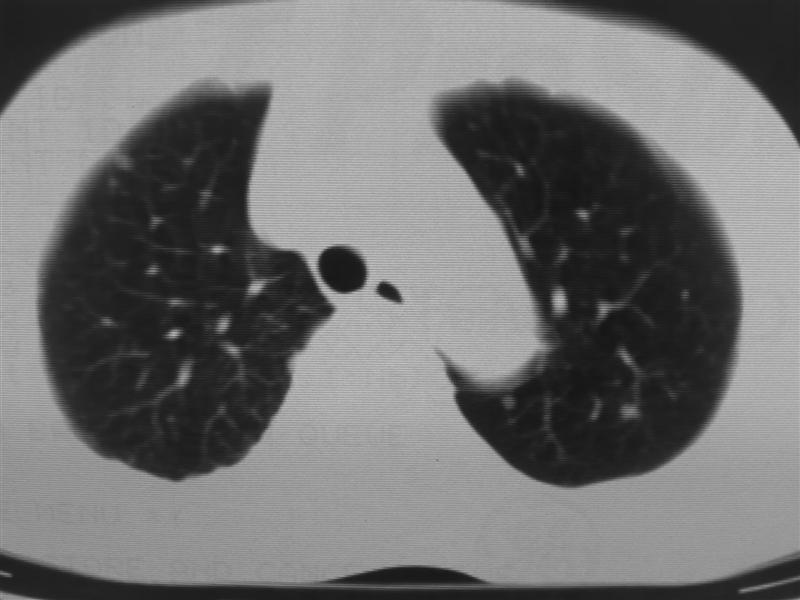

标题: CT10080:F76Y,各位老师发表高见!!! [打印本页]

标题: CT10080:F76Y,各位老师发表高见!!!

右下肺周围型肺癌伴双肺右侧叶间 胸膜及右肺门淋巴结转移

肺癌肺内转移。

肺癌、肺及胸膜转移可能性大;tb不除外